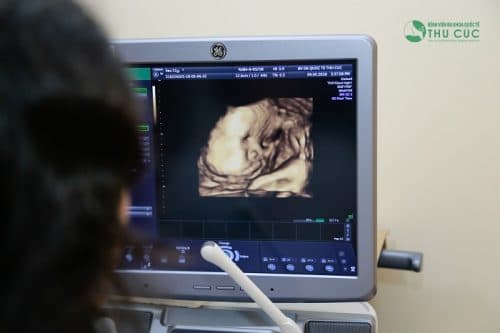

Siêu âm: Theo các chuyên gia phụ sản ba thời điểm cần thiết để tiến hành siêu âm thai theo dõi hình dáng và sự bất thường của thai nhi là tuần thứ 12, 22 và 32.

- Siêu âm là bước đầu tiên trong quá trình sàng lọc thai nhi

Khi thai nhi vào tuần thứ 11 – 13, các bác sĩ sẽ siêu âm để đo độ mờ sau gáy nhằm sàng lọc một số dị biến về nhiễm sắc thể gây bệnh Down, dị dạng tim, tay chân,…Sau tuần thứ 14 chỉ số này không được chính xác nữa.